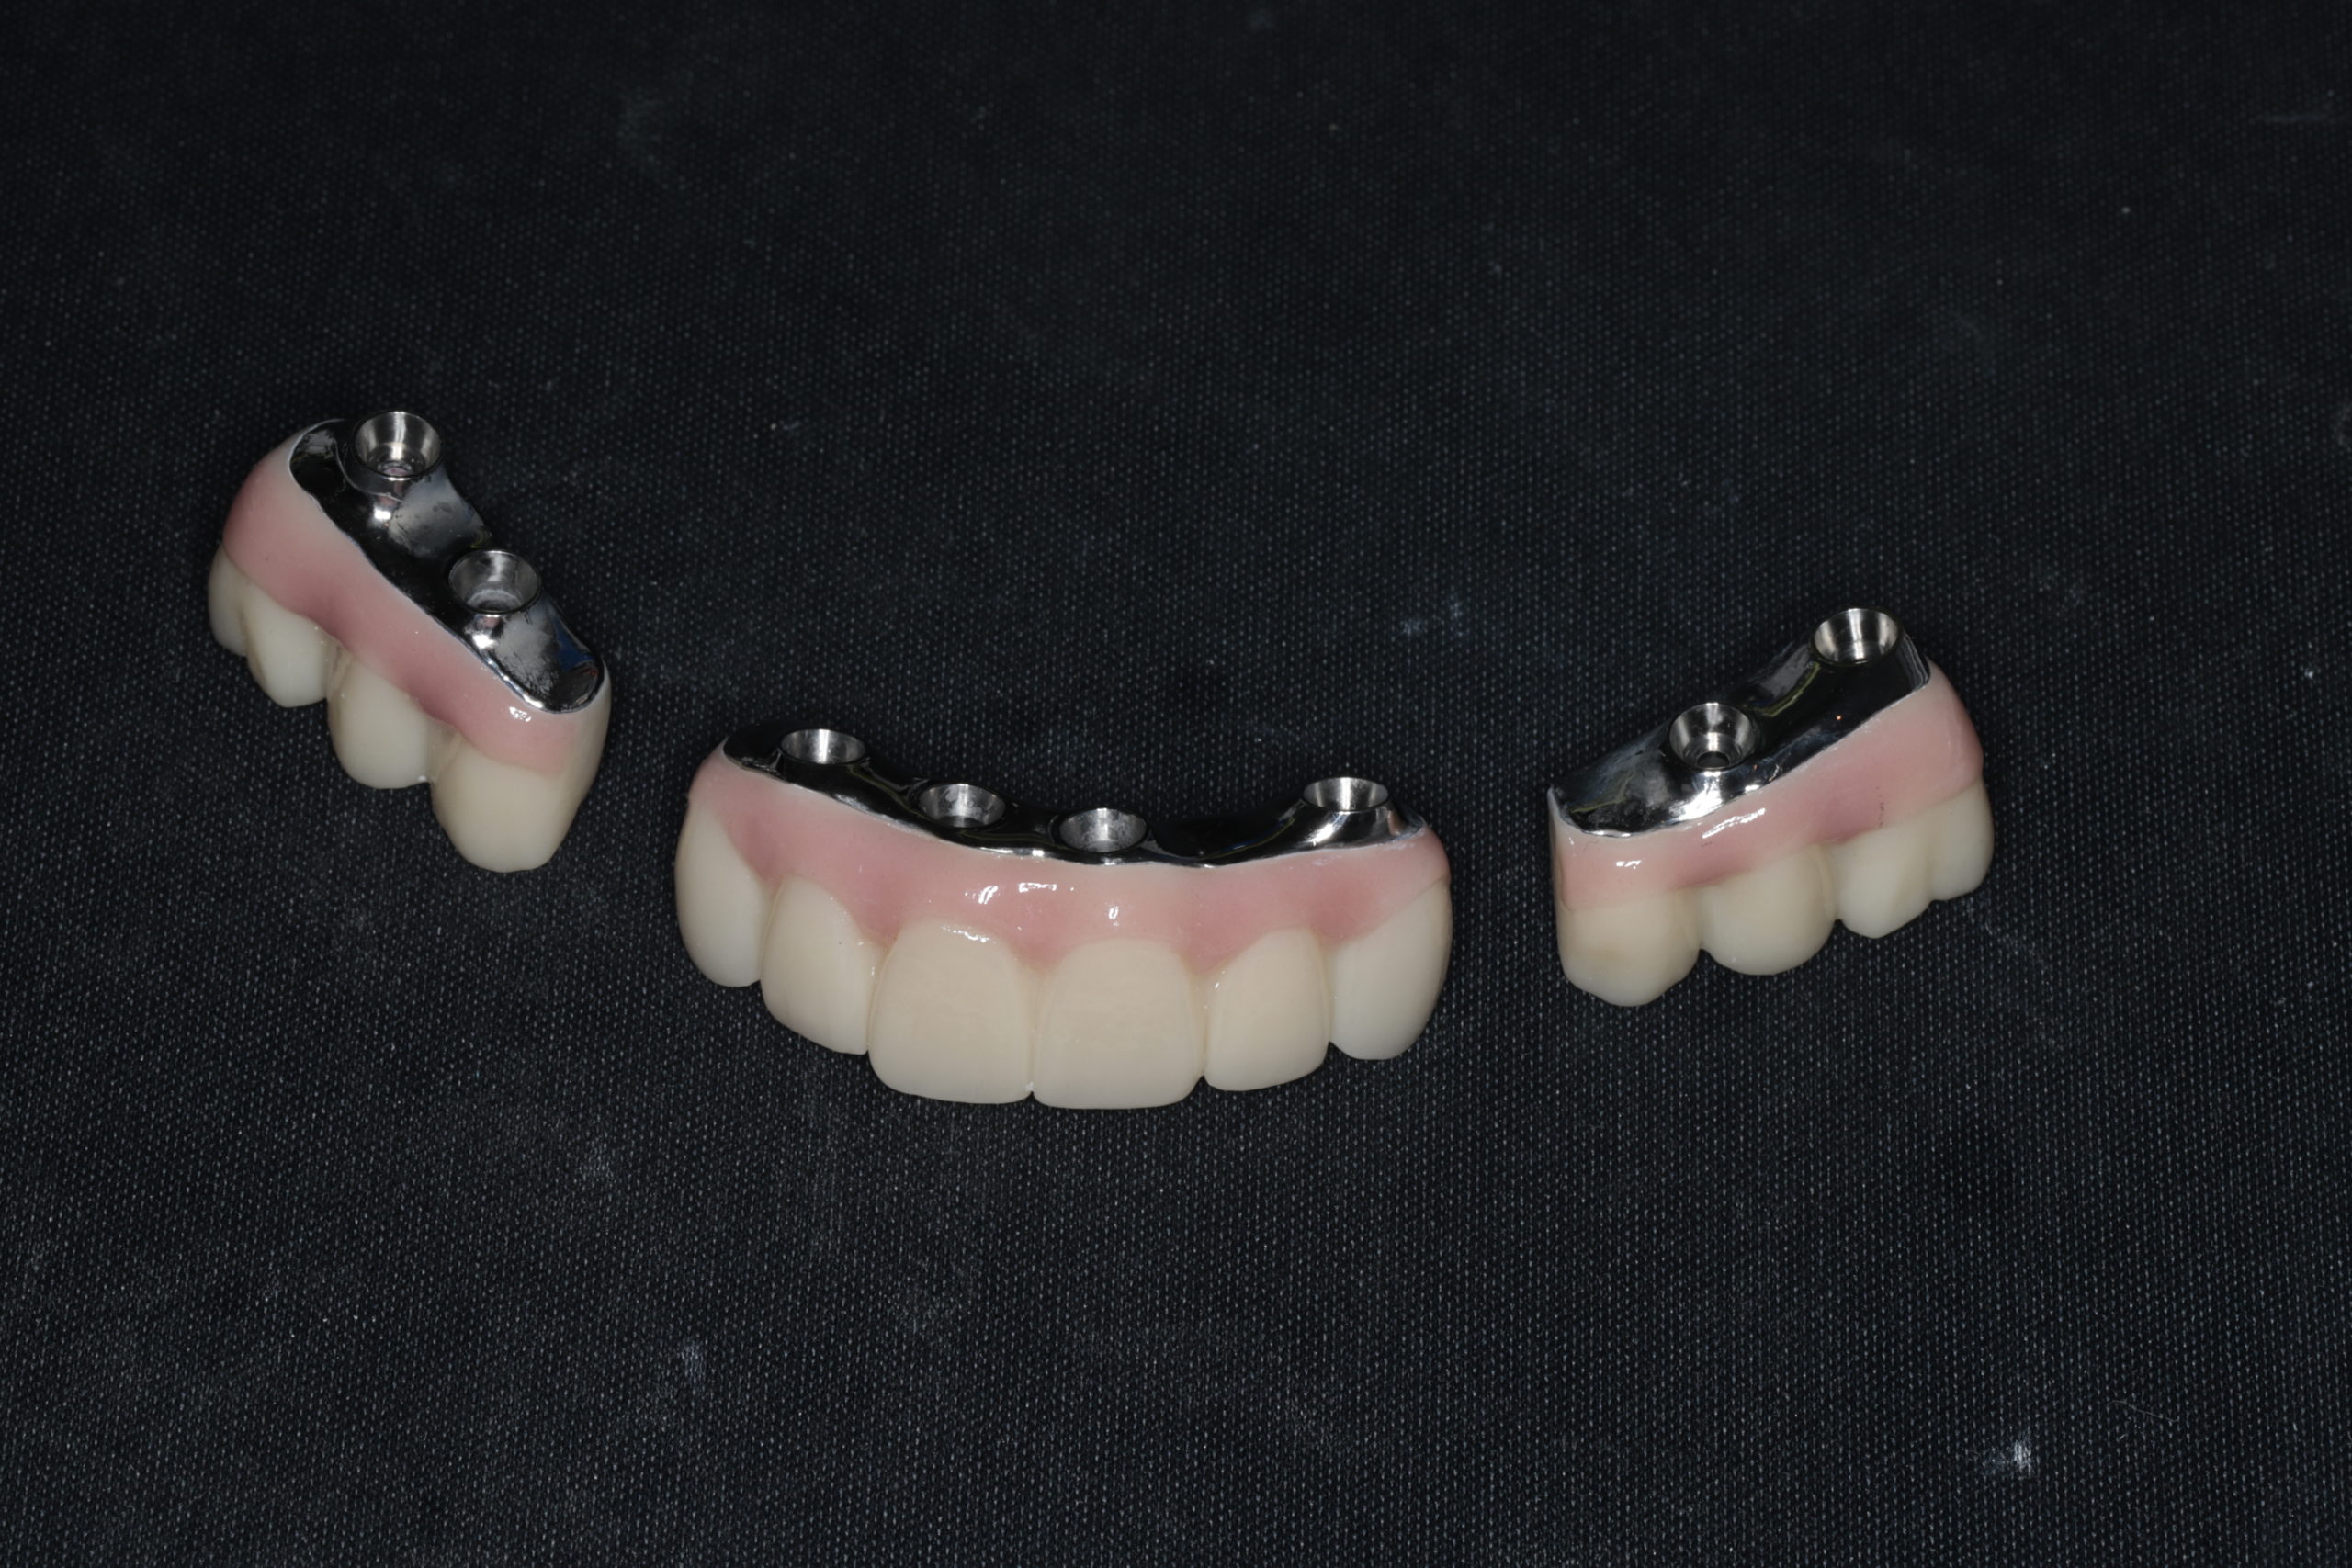

- 假牙未來做成分段式的牙橋,對於清潔有比較大的幫助

- 整個牙弓有六支以上的植體,未來若單支植體喪失,能修改假牙設計,避免再次手術

這份技術讓石先生在手術當天就完成了臨時假牙的製作,不僅立即恢復基本咀嚼功能,更讓他能維持社交美觀與自信,這對患者而言是心理壓力極大的釋放。

- 預期性更高:先穩固前牙功能後,再逐步完成後牙重建。石先生在農曆年前順利完成了所有治療,回診時他與我分享能再次安心進食的樂趣,這份穩定感是急促手術難以取代的。